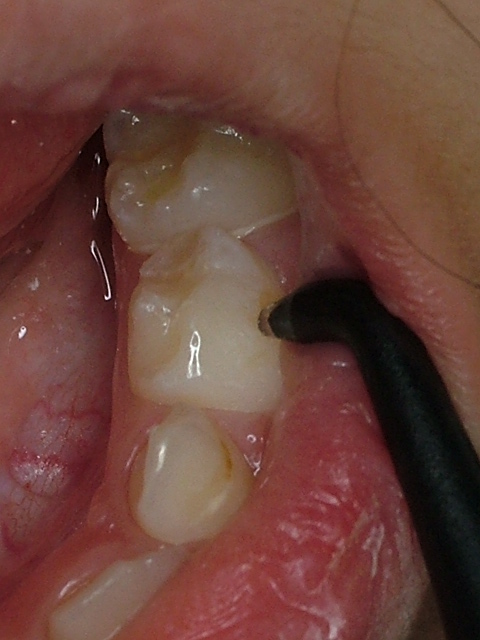

Ž•Žü•a‹Û‚Ìœ‹Û‚ð‚µ‚Ü‚·Bƒvƒ‰[ƒN’†‚ÌŽ•Žü•a‹Û‚ðŒ°”÷‹¾‚ÅŒŸ¸‚µ‚Ü‚·Bi–³—¿j

| œ‹Û‘O | œ‹ÛŒã |